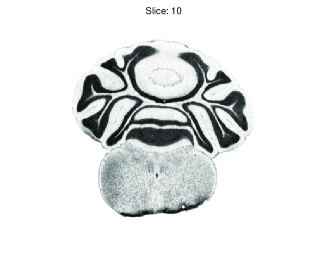

where represents a fixed radius. Note that this is not just to determine whether a specific voxel/pixel is edge or not [14]. Instead, within a specified radius , the image feature content is forced to stay beyond a variation level which prevents the registration process from getting stuck in local maxima. Edgeness maps for various slices are shown in Figure 5.

|